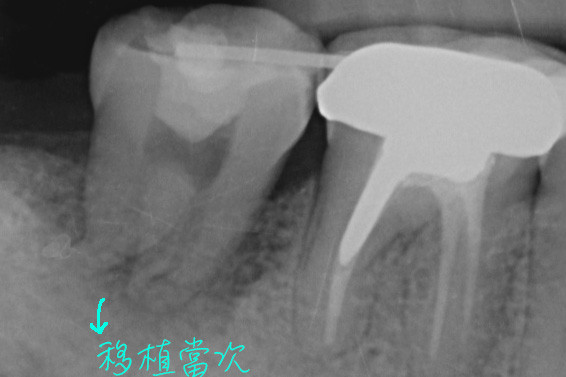

本案例的臼齒因為斷裂而必須拔除,我們把後方的智齒往前搬家,直接取代壞掉的牙齒,等到傷口癒合好後又可以正常咀嚼食物了。